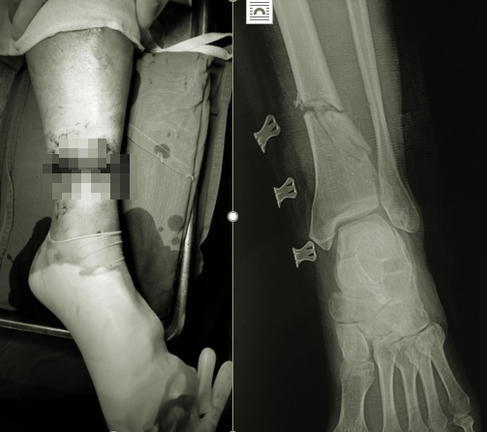

Bệnh viện Hữu nghị Việt Đức vừa tiếp nhận ông B.V.L. (56 tuổi, trú tại Hòa Bình) nhập viện trong tình trạng vết thương hở đứt 3/4 chu vi cẳng chân trái, chảy nhiều máu, mất vận động cổ chân. Các ngón chân, gãy hở xương chày, đứt hoàn toàn các gân cơ khu trước và sau cẳng chân, đứt bó mạch chày sau, chày trước.

Hình ảnh chấn thương của bệnh nhân.

Thông tin về ca bệnh, BS Hoàng Minh Thắng - Khoa Phẫu thuật Chi trên và Y học thể thao cho biết, ngay sau khi tiếp nhận, bệnh nhân được xử lý cố định ngoài xương chày, nối gân, thần kinh, nối động mạch chày trước, chày sau.

"Hiện sau mổ, tình trạng người bệnh ổn định, đầu chi hồng ấm, mạch chày trước, chày sau rõ và đang được hướng dẫn tập phục hồi chức năng", bác sĩ Thắng nói.